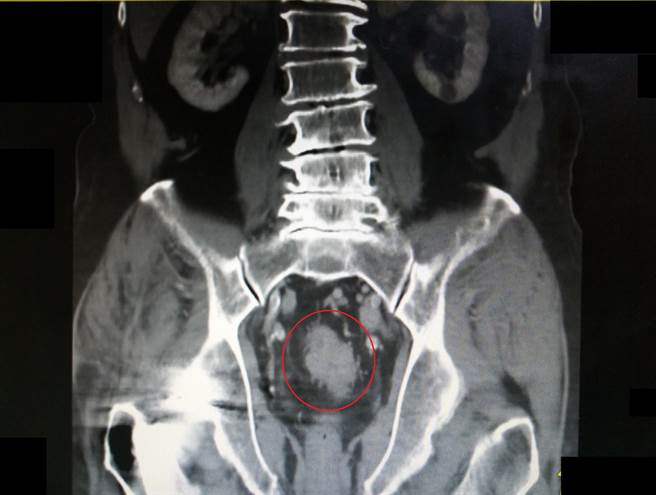

李姓老翁近日发现原本每天固定排便的习惯,变成3到5天都没有排便,或是排便时有血便的情况,到医院接受大肠镜检查后,竟发现大肠有肿瘤,切片报告显示为大肠癌第3期。

洪吉来表示,现行大肠癌的治疗方式以手术切除为主,一般较小的恶性瘜肉或肿瘤可採用内视镜切除术治疗。若肿瘤过大则需要施以结肠切除术,并依病情需要搭配化学治疗、放射线治疗或标靶药物治疗。